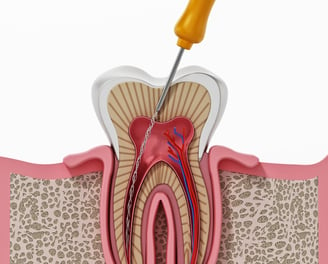

Es un procedimiento en el que se abre la cámara pulpar del diente para eliminar el tejido pulpar infectado o inflamado. Esto ayuda a aliviar el dolor y preparar el diente para un tratamiento de conducto.

Trepanación Pulpar (urgencia)

Es el procedimiento para limpiar, desinfectar y sellar los conductos internos del diente cuando la pulpa está infectada o inflamada. Es esencial para salvar el diente.

Tratamiento de Conducto